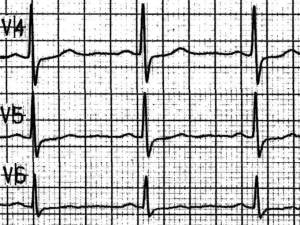

Quiz 7: Akuter infero - postero - lateraler Myocardinfarkt

73 - jähriger Rentner mit akutem infero - postero - lateralem Myocardinfarkt, 5 Stunden nach systemischer Thrombolyse.